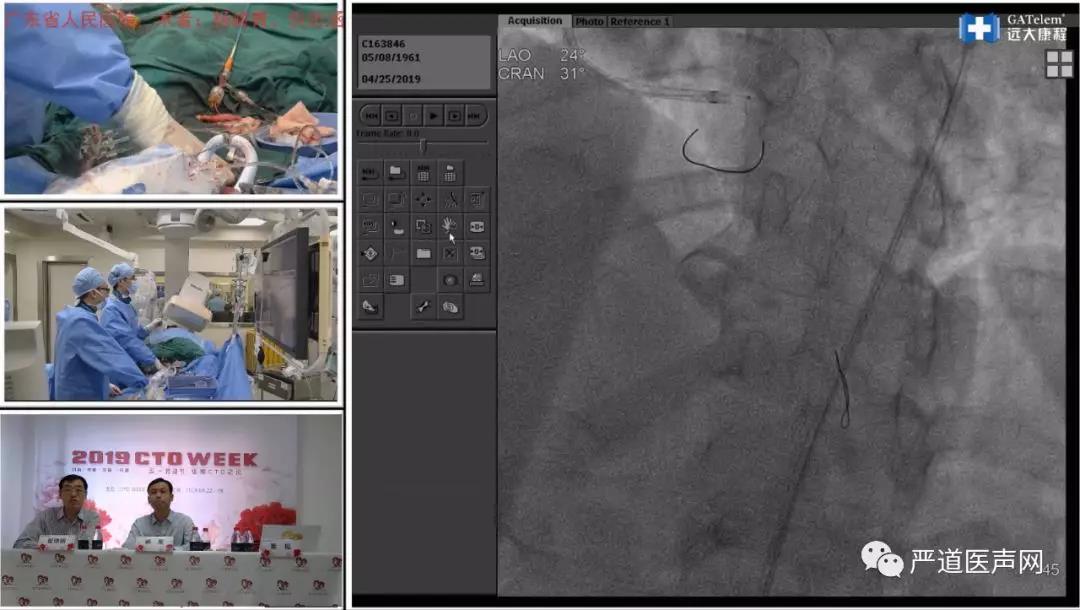

第四演播室直通广东省人民医院,进行手术演示的术者为杨俊青、倪忠涵、张斌、何鹏程4位教授。他们共演示4台手术,其中一例是日本专家已经失败两次的病例,张斌教授利用很短的时间就成功完成。看到张斌教授轻松完成手术,不少观众对其高超精湛的操作技巧表示了由衷的钦佩。彭红玉教授和王平教授分别作了题为《逆向PCI术中正向轨道的建立 》和《延长导管在CTO PCI中的使用技巧》的主题报告。